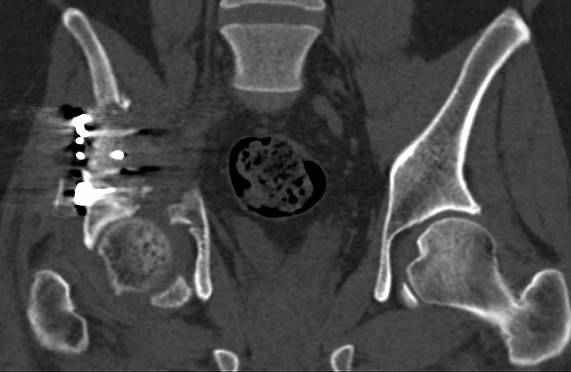

Интересно было бы посмотреть рентгенограммы до операции. У меня впечатление, что я не все вижу, что тут есть... Уважаемые Господа "тазисты" и "тазологи", к какому типу переломов вертлужной впадины по Летурнелю вы бы отнесли это случай?

Из переломов проходящих через крыло и/или заднюю стенку ни простой перелом "передней колонны" (явно имеется пером задней стенки, и не видно перелома седалищной или лонной), ни простой "поперечный", ни ассоциированный "Т-образный" (т.к есть перелом крыла и не видно перелома седалишной), ни ассоциированный "задняя колонна+задняя стенка", на ассоциированный "поперечный+задняя стенка", ни ассоциированный "передняя колонна+задняя гемисфера" (не видно перелома седалищной), ни ассоциированный "обе колонны" (не видно перелома лонной седалищной) не подходят под эту классификацию....

к таковым себя не причисляю, но...обычное дело для нашей страны - выкладывать 3D и не показывать стандартные проекции Judet. Дигност представляет те ракурсы, которые по-его мнению наиболее информативны, более того комп сам достраивает какие-то мелкие повреждения по 3D по своему усмотрению. По данной реконструкции можно предполагать высокий двухколонный перелом с оскольчатыми передней и задней колоннами, оскольчатую высокую переднюю колонну с задним полупоперечником или одно из перечисленных с вовлечение КПС. У меня впечатление за второй вариант, но нужно обследовать нормально - проекции, сканы.

высылаю дополнительно сканы.

итак, второй вариант: высокий двухколонный с вовлечением КПС... Ни одно из основных повреждений не репонировано, кроме задней стенки. Скорее всего попытка реконструкции вертлуги сейчас будет очень травматичной и не очень эфективной, т.е. вероятный риск более значим, чем ожидаемая польза... Лучше подождать, и потом сразу эндопротез